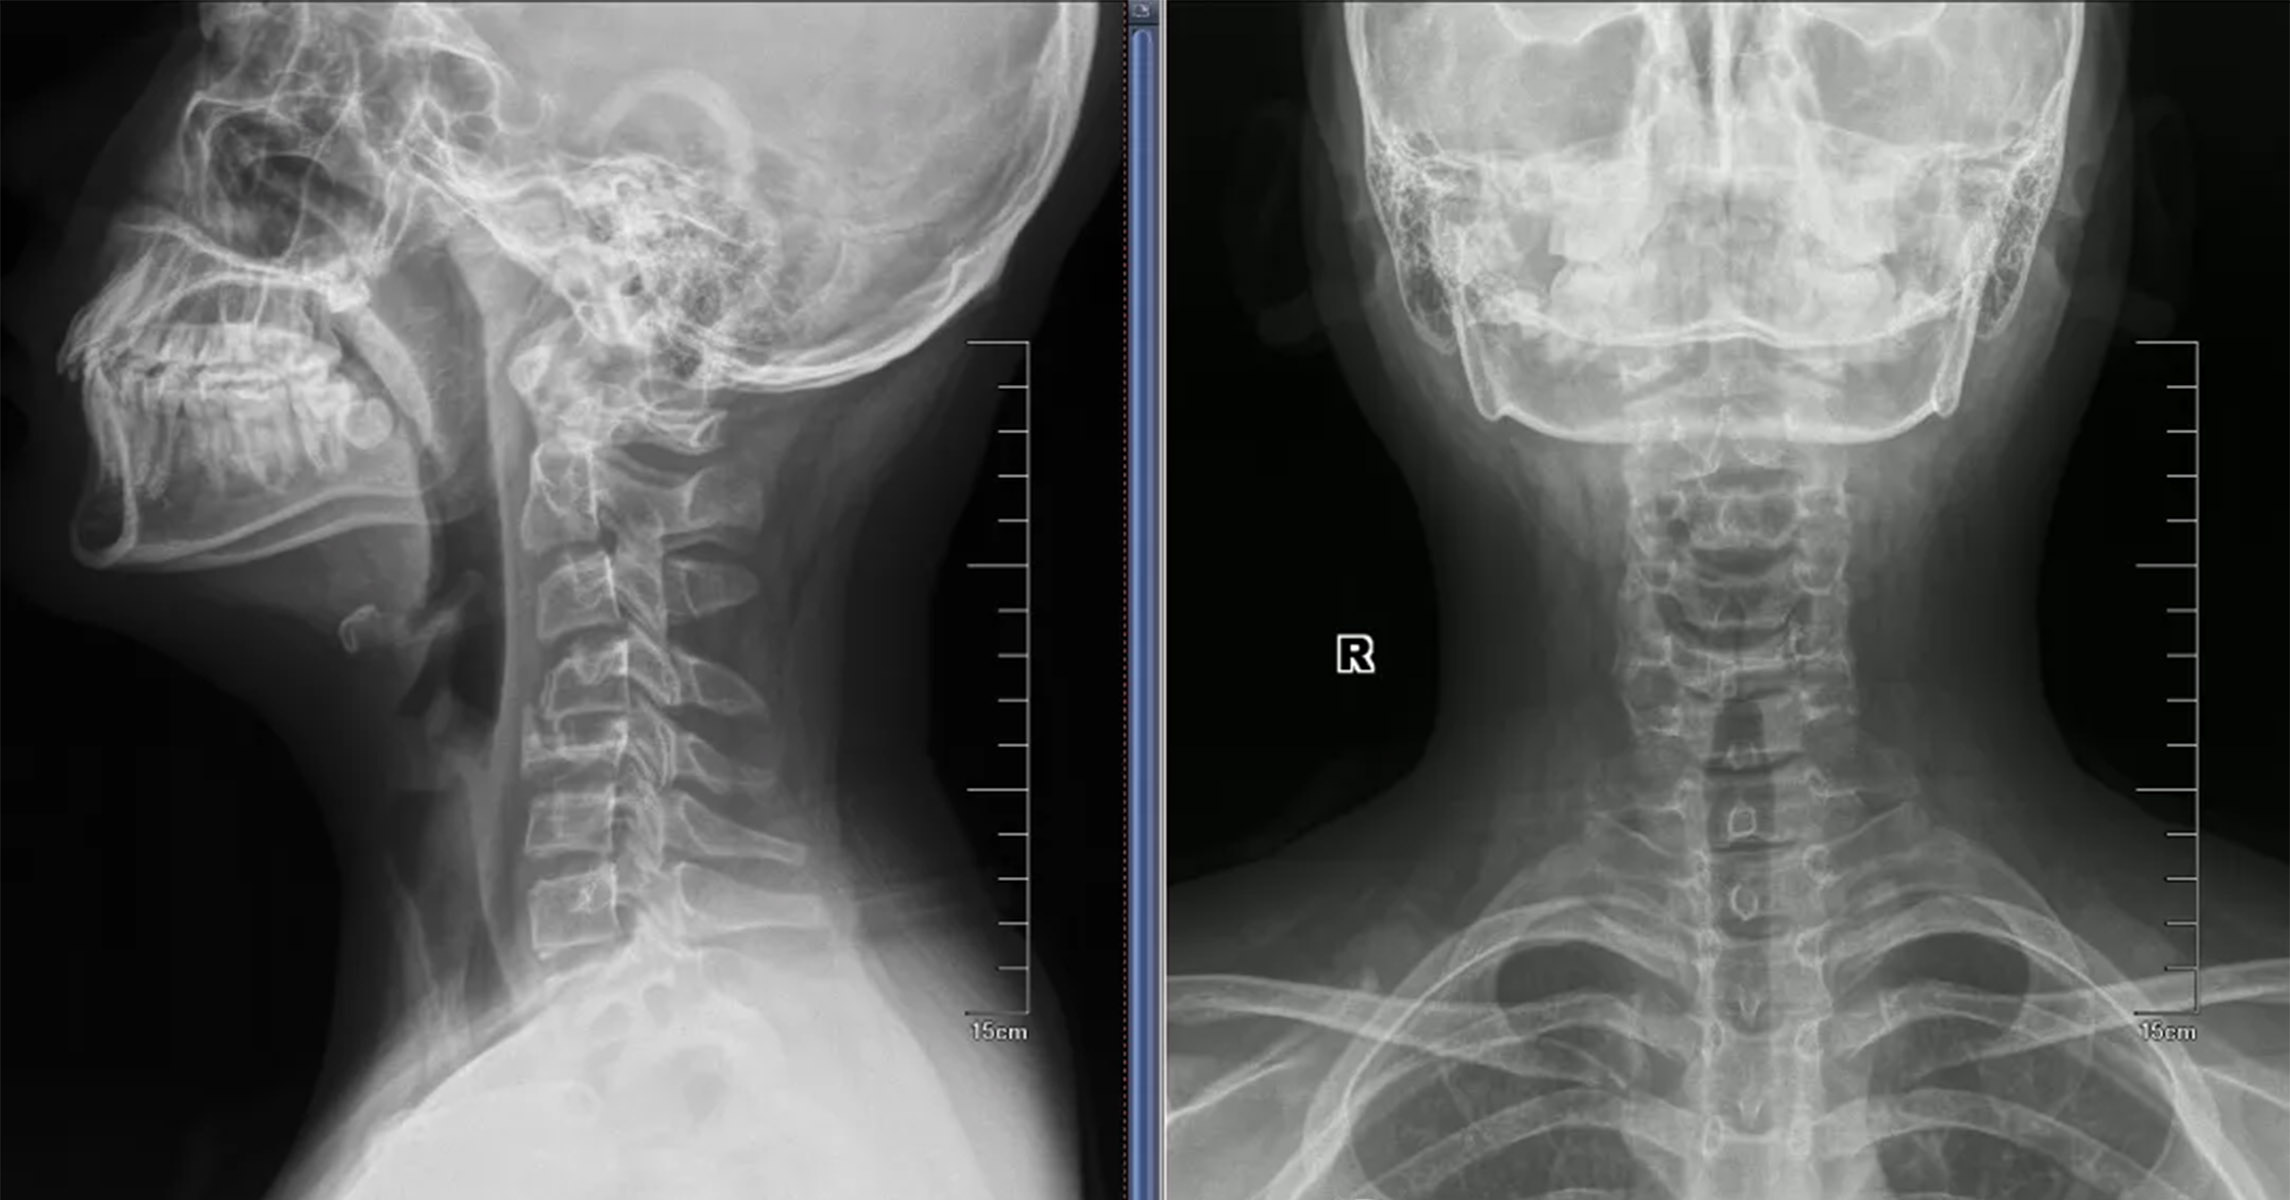

朗格汉斯细胞组织细胞增生症(LCH)是一种涉及朗格汉斯细胞克隆增殖的罕见疾病,其特征是组织细胞(被激活的树突状细胞和巨噬细胞)的异常增殖。该病与其他形式的白细胞异常增殖有关,可分为局部的骨嗜酸性肉芽肿(EG)和罕见的多系统综合征。 骨嗜酸性肉芽肿在骨肿瘤中的占比不到1%,好发于婴幼儿及青少年,尤其是10岁以下的儿童;好发部位为颅骨、下颌骨、脊柱、肋骨和长骨。其发病机制尚不清楚,可能与病毒、细菌、遗传因素及免疫功能障碍有关。实验室检查结果提示血沉加快、白细胞增多或嗜酸性粒细胞计数增多等。 四肢嗜酸性肉芽肿最常发生于股骨,然后为胫骨,之后为肱骨;病灶发生的位置多为骨干,其次是干骺端,发生于骨骺者极为少见。典型X线表现为穿孔型溶骨性病变,无反应性硬化症;存在较为成熟的骨膜反应,骨膜反应与骨皮质间可见透亮线,无放射状骨针形成;可伴有范围较广的软组织肿胀,但其边界清晰,密度和信号较均匀。 鉴别诊断:浆细胞瘤、多发性骨髓瘤、软骨炎等。 脊柱嗜酸性肉芽肿最常见的发病位置是胸椎,然后是腰椎和颈椎。临床症状取决于病变椎体的位置,常见症状有背部或颈部疼痛,进行触诊时脊柱有压痛和活动范围受限,或斜颈。病椎椎体骨质呈溶骨性破坏,进行X线检查时可以观察到椎体的密度不均伴空气影,形态呈楔形改变,椎间隙正常或增宽,典型表现为“扁平椎”。患者进行CT检查时,医生可以清楚地观察到早期椎体以溶骨性破坏为主,病灶周围可见不规则的斑点状骨性残片,晚期以骨质硬化增生为主,在缺损的骨质边缘可伴有硬化增生,出现混杂的密度改变。椎体可呈现“扁平椎”或楔形改变,椎旁可见软组织肿块影分布。MRI(磁共振)检查结果提示,早期椎体信号的异常改变以及软组织肿块的侵袭,随着病程的进展,椎体严重破坏呈“扁平椎”或“铜板椎”;软组织肿块在椎体周围分布,其信号变化基本与病椎一致,具有一定的特异性。 鉴别诊断:尤因肉瘤、骨肉瘤、淋巴瘤、转移瘤和成骨不全等。当临床症状和影像学表现不明确时,患者需要做组织活检。根据活检结果,医生进行组织学诊断。CT引导下的活检对嗜酸性肉芽肿的组织学诊断是有效的,诊断准确率为70%~100%。 骨嗜酸性肉芽肿的治疗方法包括观察和固定、吲哚美辛治疗、甲基强的松龙注射、射频消融术、局部切除和刮除伴或不伴植骨、化疗和放疗,复发率低于20%。1.无症状患者典型单发病灶可选择保守治疗;脊柱孤立嗜酸性肉芽肿伴轻度神经症状者,可进行固定和放疗,低剂量放疗可有效限制疾病进展,但是可能损害软骨内生长板,限制骨愈合和重建,或导致放射引起的继发性疾病,如放射后肉瘤和脊髓炎。2.朗格汉斯细胞悬液可产生白细胞介素(IL)和前列腺素(PG),甲基泼尼松龙可抑制IL-1诱导的骨吸收和前列腺素生成,对于小于受累骨直径一半的小病变,建议最低剂量为40毫克,对于骨盆的大病变,建议最高剂量为160毫克。3.单发嗜酸性肉芽肿不推荐化疗;化疗应到全身累及时进行,或作为儿童单发病灶无法进行安全、完整的手术切除时的初始治疗。4.若保守治疗效果不佳,出现严重的脊柱后凸畸形或神经功能损伤,应尽早采取手术治疗。手术治疗包括开放性手术和微创手术,脊柱嗜酸性肉芽肿的开放性手术指征主要为:神经症状明显,脊柱稳定性差,畸形严重,保守治疗无效且病程进展较快等。微创手术包括经皮椎体成形术和CT引导下经皮穿刺注射药物;适应证主要为疼痛症状明显,脊柱压缩但神经症状不明显,脊柱稳定性好。 病例:孙某,9岁,男,因“颈部间断疼痛伴活动受限3周,加重1周”入院。患儿3周前无明显诱因出现颈部轻微疼痛,伴轻度活动受限,四肢运动、感觉正常,未在意,未进行诊治。1周前,患儿颈部疼痛伴活动受限加重,到医院就诊。颈椎CT检查结果提示:C4椎体内骨质破坏。患儿来到河南省肿瘤医院就诊,入院后完善相关检查。根据检查结果,医生考虑C4嗜酸性肉芽肿。对患儿予以卧床、颈椎牵引、口服强的松治疗3周,其颈部疼痛明显好转。患儿进行颈椎CT复查,未见病变进展。嘱咐患儿出院后佩戴颈托,继续用药,定期复查。 (作者供职于河南省肿瘤医院)